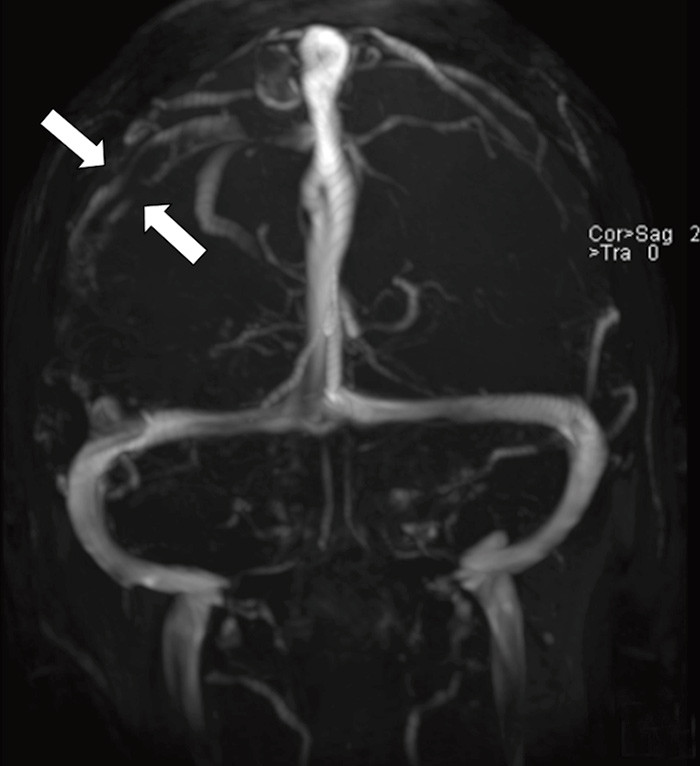

A previously healthy woman in her 40s suffered morning headache and vomiting the day before admission. She was a non-smoker and used no medicines or hormones. On the following day she developed acute left facial paresis, left arm paresis and dysarthria. She experienced transient spasms in the left part of her face. Cerebral CT performed at the local hospital showed a high-attenuation lesion in the right temporoparietal lobe (see online version for picture). D-dimer was 0.8 mg/l (normal < 0.4). A vascular event in the right hemisphere was suspected. Cerebral MR venography at the university hospital the following day revealed an intraluminal venous thrombus corresponding to the right vein of Trolard (left picture). Diffusion-weighted cerebral MRI showed a mix of vasogenous and cytotoxic oedema in the temporoparietal region, typical of a venous infarction (right picture). Tests of thrombocoagulation system function revealed activated protein C resistance 0.66 (normal 0.85 – 1.15). The patient received anticoagulant therapy and six days later follow-up cerebral MR venography showed normalisation. She was discharged without sequelae.

Cerebral venous thrombosis often presents with severe headache and may cause focal neurological impairment and epileptic attacks in the presence of an infarction. Activated protein C resistance predisposes for cerebral venous thrombosis, which is a rare (0.5 – 1 %) cause of cerebral infarction (1). Early diagnosis and treatment are essential for a good clinical outcome. CT and MR venography enable non-invasive visualisation of venous cerebral thrombosis with a high degree of sensitivity and specificity.